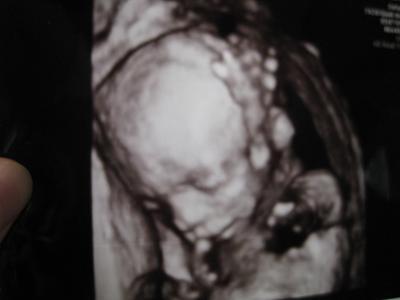

hello! ich möchte hier mit euch mein schönes bildchen teilen! ich finde ja die 3d bilder immer etwas beängstigend.. naja, aber dieses hier ist doch ganz süß! ;) es sieht nur so aus, als hätte mein baby eine delle an der nase, meint ihr das täuscht? ;) es hat sich gezeigt, dass ich einen 2ten jungen bekomme! :) freu mich riesig, es war insgeheim mein wunsch, auch wenn mein gefühl eher richtung mädchen ging. ging es bei meinem ersten aber auch schon. er wiegt ca 300gr und ist 22cm lang. er hat es sich wirklich gemütlich gemacht und war anfangs kaum aus der reserve zu locken. ich spür ihn mehrmals täglich, auch nachts wenn ich mich umdreh. mir tut immer alles weh, muss mich oft von einer seite auf die andere drehen, und er muss sich dann auch neu positionieren. kennt ihr das auch? rückenlage geht garnicht mehr. dabei ist mir der bauch einfach auch zu steinhart. er wird ständig hart. deswegen soll ich lieber magnesium nehmen, lt. FÄ. naja.. ich steck auch zusätzlich noch in einer emotionalen krise, weiß garnicht weiter und steh ganz allein da. aber das schaff ich auch dieses mal. davon geh ich aus. aber leicht ist es dennoch nicht. freu mich euch zu haben, auch wenn ich meist eher still bin. :)

Was für ein süßes Bild!! Die "Delle" verschwindet bestimmt noch. Es ist ja alles noch ganz weich und im Wachstum. Wenn Du Kummer hast, kannst Du ihn gerne bei uns (oder im April Treffpunkt - ist dann nicht so öffentlich) abladen. Vielleicht hilft Dir das aufschreiben schon etwas. Außerdem hab ich hier schon ganz tolle Antworten und Motivationen gelesen :) Alles Gute für Dich und Deine beiden Jungs!

die delle ist nur ein darstellungsproblem, die wird später nicht zu sehen sein :o) glückwunsch zum outing!!!! halt die ohren steif, ich hoffe es geht dir bald besser!!!

Hey erstmal Gratuliere ich zum Outing! Und das 3D Bild ist ja voll süß, wahnsinn das man da echt alles schon so gut erkennen kann. Keine Sorge wegen der Delle, das war bei einer Freundin von mir auch und der kleine hat eine komplett schöne Nase ;-) das kann auch immer täuschen. hab auch schon gelesen keine Ahnung obs stimmt, man sollte sich einen Tag vorher nicht mit Öl den Bauch eincremen da es Schatten verursachen kann..... obs stimmt weiß ich nicht^^ hab ich so sonst noch nie gehört aber naja im Internet findet man ja einiges ;-) das mit dem schlafen hab ich auch muss mich auch ständig drehen Rücken geht auch gar nicht mehr...hab dann komplette Schmerzn in der Gebärmutter bzw. in den Bändern.... so wende ich mich von links nach rechts. Mir tut der Oberschenkel Knochen jeden Tag so weh wenn ich aufstehe. Magnesium nehme ich auch, da ich die Dehnungsschmerzn eben stark spüre! Ich hab nächste woche meinen großen Ultraschall kanns auch kaum mehr erwarten und wahnsinn wie groß die schon sind ;-)